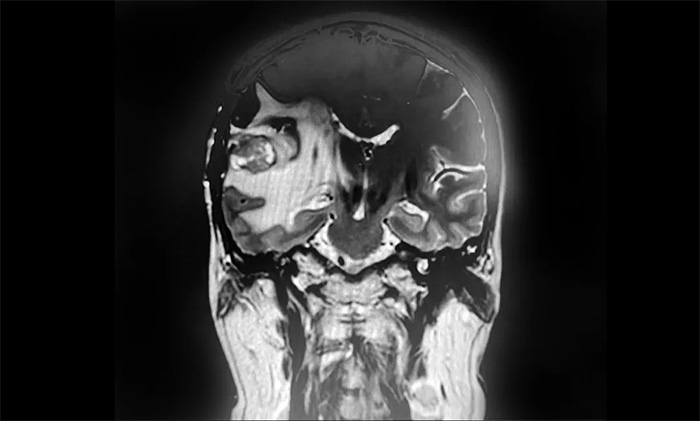

盧云鶴博士為患者進(jìn)一步完善檢查。MR檢查示右側(cè)顳葉內(nèi)見環(huán)片狀混雜信號(hào),大小約20mm*18mm,強(qiáng)化與水腫明顯。周圍腦溝、裂顯示欠清;右側(cè)側(cè)腦室受壓變形,中線結(jié)構(gòu)稍左偏,出現(xiàn)可疑腦膜轉(zhuǎn)移。

▲ MR示右側(cè)顳葉占位,占位效應(yīng)明顯

結(jié)合既往病史和影像學(xué)表現(xiàn),盧云鶴博士認(rèn)為,患者乳腺癌腦轉(zhuǎn)移瘤復(fù)發(fā)可能性較大。雖然占位本身體積不大,但其水腫帶已壓迫臨近腦室,患者出現(xiàn)頭痛頭暈癥狀,應(yīng)考慮采取合適的方法積極給予治療。